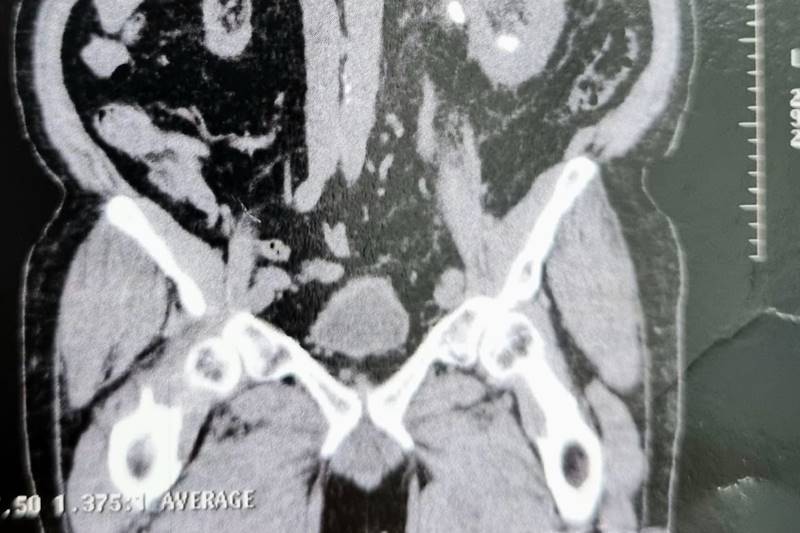

A grande maioria dos cálculos são de pequeno tamanho (menores de 5mm), não havendo necessidade de tratamento cirúrgico. Contudo, em cálculos de maior dimensão, sua eliminação torna-se improvável havendo necessidade de cirurgia.

Hoje o Hospital Marques Basto dispõe de tecnologia para o tratamento minimamente invasivo de cálculos. São utilizados aparelhos para entrar na via urinária, seja no rim ou no ureter (canal que comunica rim com a bexiga), permitindo a fragmentação com laser. São procedimentos de maneira geral seguros que possibilitam apenas 1 dia de internação e retorno precoce ao domicílio ou trabalho.